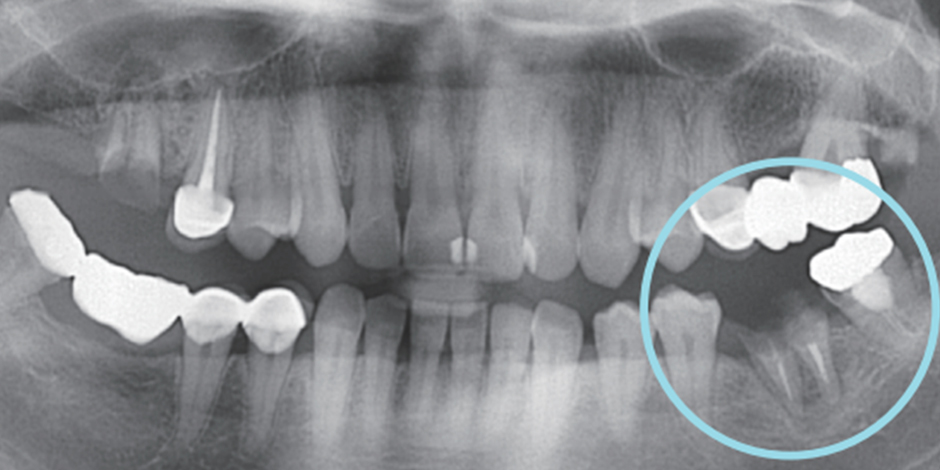

신경치료 후 크라운, 필수입니다.

신경제거 후 신경으로부터 받던 영양분을 공급받지 못해 약해진 치아는 작은 충격에도 금이 가거나, 부러지거나, 깨져버리기 때문에 단단한 크라운을 씌워 치아를 보호해야 합니다.

신경치료를 위해 치아가 아래ㆍ위 치아가 닿지 않게 조절을 하며 치아에 구멍을 뚫어 놓기 때문에

씌워야 기능을 수복할 수 있습니다.